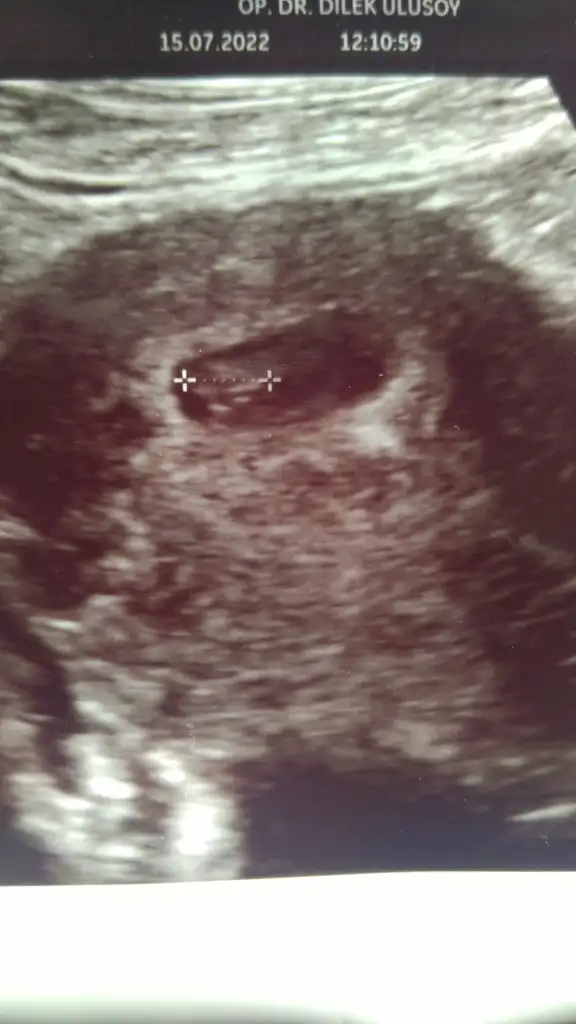

Bebegin Kesedeki Konumuna Göre Cinsiyet Tahmini

Kızlar merhabalar , bana da tahmin yapabilirmisiniz :) ve neye göre söylüyorsunuz onu da çok merak ediyorum yazarsanız çok sevinirim :) 11+4 üz